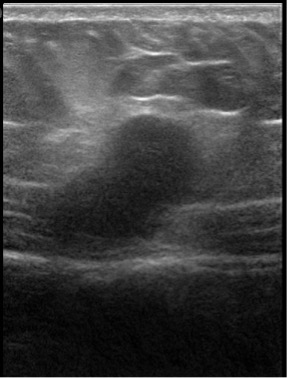

Results of an abdominal examination revealed a deep-seated, firm to hard mass with indistinct margins that appeared to be arising from or firmly attached to the anterior abdominal wall muscle. Results of an ultrasonography scan suggested a probable cystic mass in the subcutaneous tissues of uncertain etiology (Figures 1 and 2).

Figure 2. An ultrasonography scan of the abdomen revealed a mass to the right of the midline in longitudinal orientation, measuring 3.04 × 1.65 cm.